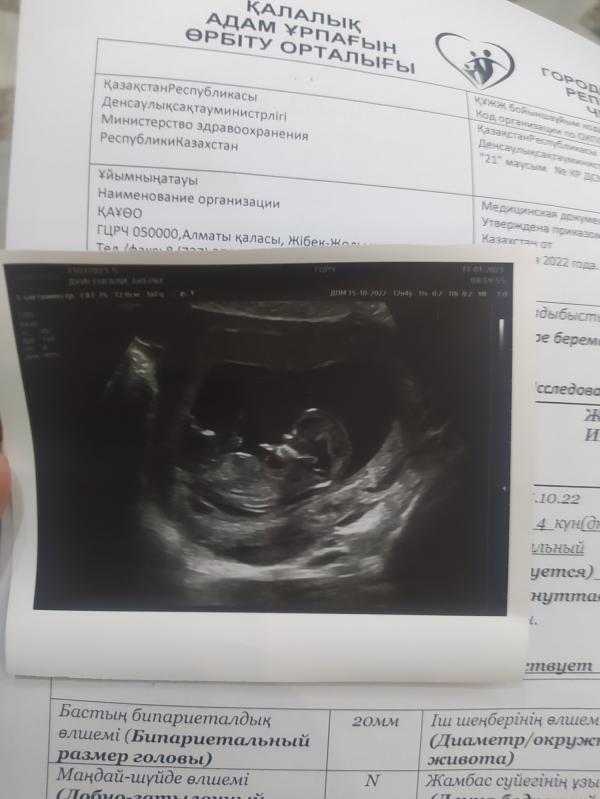

С ребенком всё хорошо🙌🏻 До этого сильно переживала, из за того что болела ковидом при овуляции и пила антибиотики. Ой пинается сильно, еле-еле посмотрели .

Да чуствую прям, ещё по Узи видела как пинается, ещё апарат пинает и руками двигает😂 Узист говорит да у вас шустрый ребёнок, не даёт себя смотреть)